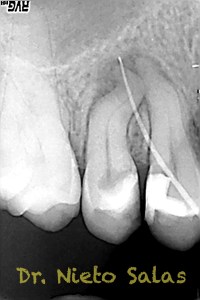

Y  de forma muy similar en el caso B; en este caso el paciente vino a la revisión a los 9 meses evidenciado el éxito en el tratamiento:

Con respecto a lo puramente endodóntico, la verdad que fueron unos casos de verdadero estrés para no perder la permeabilidad ni la long de trabajo, con técnica corona-apice y con un diametro apical de 20, instrumentado solo la parte apical con limas de Mtwo , la parte coronal me ayudé de ultrasonidos. No sé, que más contarte con respecto a la conformación de los conductos.

La verdad, no me planteé la posibilidad de la obturación con Thermafil, se trataba de un caso con un sistema de conductos con un itsmo coronal, y pienso que la obturación con sistema de ola continua me garantizaba un mejor sellado.